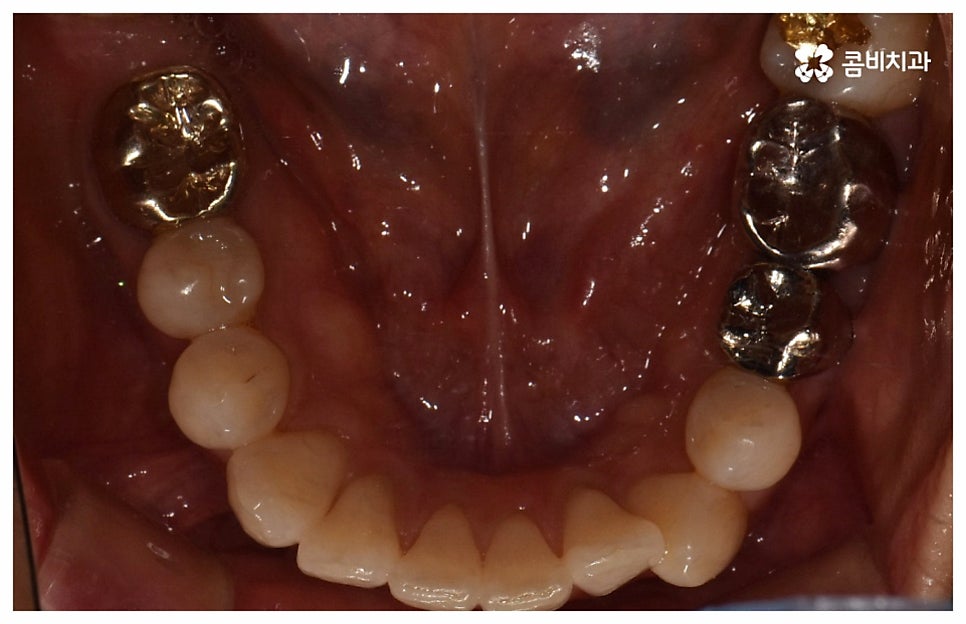

그래서인지 자기 관리의 일환으로 외모를 가꾸고 치아 건강을 증진시키기 위해 중년치아교정 을 고려하시는 분들도 늘어나고 있어요. 치열이 삐뚤어지고 교합이 잘 맞지 않는다면 교정 치료를 통해 이를 바로잡아 저작 기능을 향상시키고 발음을 정확하게 할 수 있으며, 심미적으로도 호감가는 인상을 만들고 추후 치아 관리도 보다 수월하게 할 수 있도록 도움을 받을 수 있기 때문에 이에 대한 수요가 많아지고 있는 거예요.

나이가 들어가면서 치아와 주위 조직들이 약해질 수 있고 치주 질환이 발생할 위험도 높아지기 때문에 중년치아교정 치료시 환자분들의 상황에 따른 맞춤 진료를 더욱 세심하게 진행할 필요가 있어요. 교정 방법이나 주의점에 대해서 꼼꼼하게 확인하고 계획을 세워야 할 뿐 아니라 교정 치료 전에 충치나 잇몸병과 같은 구강 질환이 발견되었다면 이를 미리 깨끗하게 치료하고 진행 과정 중간에도 장치에 음식물 찌꺼기가 끼지 않도록 위생 관리를 철저하게 해주며 치료 후 치아와 잇몸이 약해지지 않도록 환자분들 각각의 치아 이동 속도에 따라 무리하지 않는 것이 중요한 포인트라고 할 수 있습니다.

이때 환자분들에 따라 치열을 가지런하게 만들기 위한 구강 내 공간이 부족하다면 발치를 해야하는 경우도 있는데 혹시 평상시 상용하는 약이 있는 분들은 미리 의료진에게 얘기하고 복용 스케줄을 조절 하시는 게 좋을 거예요. 또한 골다공증이나 관절염, 당뇨 등 만성 질환을 앓고 있는 분들의 경우 치아 이동 속도가 더욱 더딜 수 있으므로 이에 대해서도 충분히 인지하실 필요가 있어요.